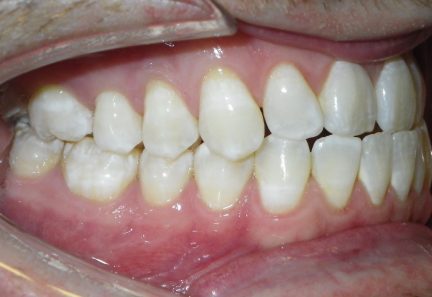

État final

- Relation de classe III maintenue

- Surplomb et recouvrement normaux atteints

- Lignes médianes coïncidentes

- Tous les objectifs du traitement ont été atteints cas

- Des arcades harmoniques ont été réalisées

- La béance antérieure de classe III a été corrigée par une combinaison d'égression active absolue des dents antérieures supérieures ainsi que d'une inclinaison des incisives

- La rétraction des dents antérieures inférieures en utilisant l'espace existant ainsi que l'espace gagné en effectuant une réduction interproximale et avec l'usure élastique de classe III ont contribué à la correction de la béance antérieure